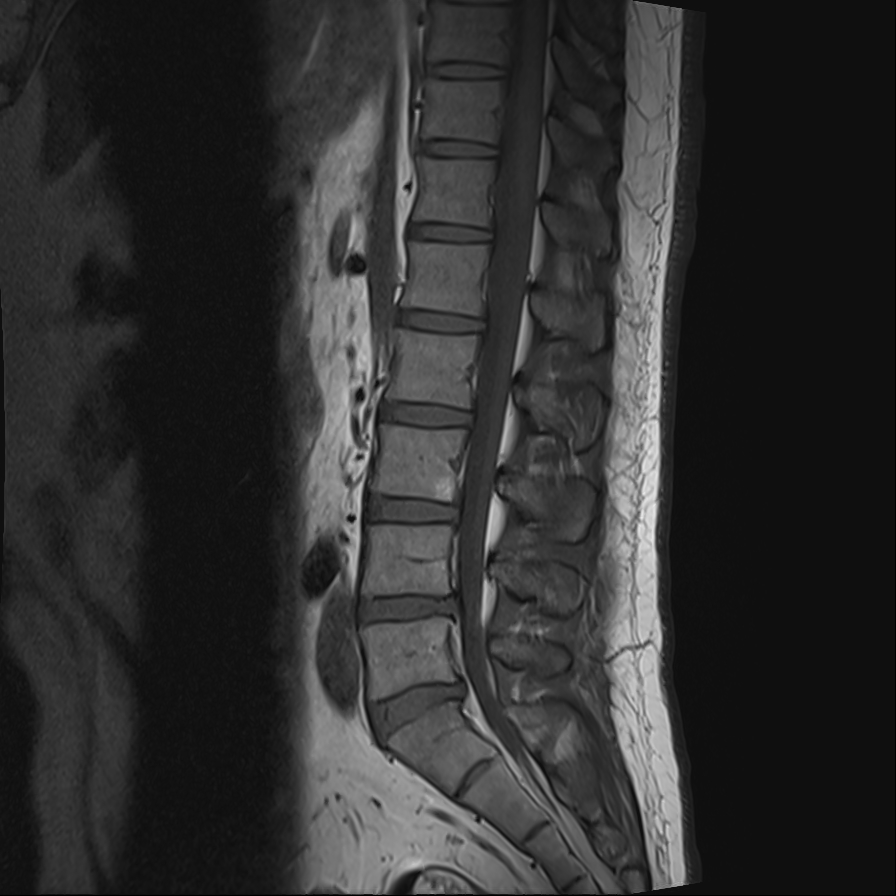

위 사진이 바로 제 허리 사진입니다.

하지만, 분명 병원에 첫 방문했을 당시 4~5번 디스크가 조금 튀어 나오기는 했으나 수술을 요하는 단계까지는 아닌 것 같고 아직 사회활동도 해야 하니 주사를 맞아보고 불가피할 경우 시술로 진행하는 것이 좋겠다고 이야기했었는데 2차례 주사를 맞은 뒤에는 수술 이야기를 꺼내서 신뢰가 가지 않았고, 인터넷을 검색해보니 디스크가 무척 심해서 수술을 한 사람도 수술 후 다리저림 현상으로 고생하고 있다는 이야기가 적지 않아서 수술을 거절했습니다.